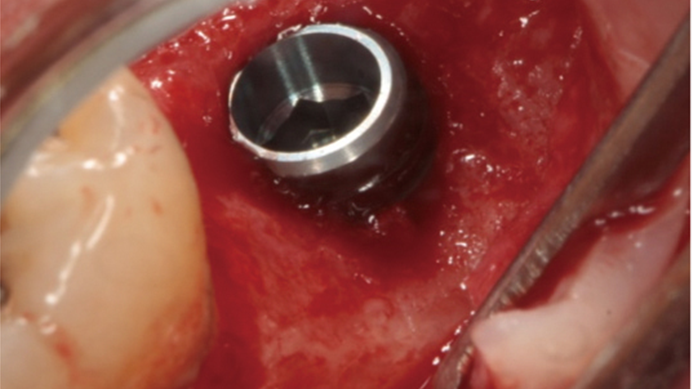

Clinical case: # 46 implant placement & GBR using i-Gen membrane for significant vertical resorption & mixed bone defect

- Courtesy of Dr. Iulian Filipov, Romania -

Keywords

AnyRidge, mandibular posterior, i-Gen, resorption, bone defect, bone regeneration, space management, #46, GBR, Dr. Iulian Filipov

Products:

AnyRidge implant system, i-Gen

“AnyRidge KnifeThread achieves excellent stability in regenerated bone & even in only 3mm bone height!”